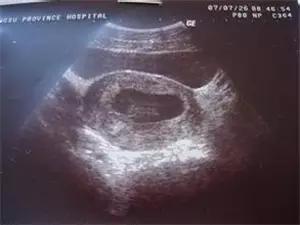

原则上在孕40天时,我们就可以通过阴道超声,观察到宫内的孕囊,在孕45天时,看到胚芽和胎心搏动。

如果此时血清HCG >1000 IU ~ 1500 IU,B超还没有看到宫内的典型孕囊,就基本肯定异位妊娠的诊断,需要留院观察,动态超声检查,看输卵管和其它部位是否出现孕囊和胎心。

因此,在这个怀孕阶段,不要拒绝超声检查,即使HCG的检测水平只有几百单位, B超没有见到宫内孕囊,都要密切观察是否宫外孕可能。

胚胎停止发育的诊断比起宫外孕的诊断要容易得多,早孕期血清HCG水平低下,翻倍试验异常,B超观察到宫内有孕囊,有的也看到胚芽和卵黄囊,但在孕45~50天还没有见到胎心搏动,延长观察了1~2周,还未见胎心。